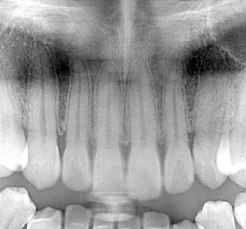

Similarly, with the mandibular anteriors, viewing the original panoramic shows lack of clarity in the apices.